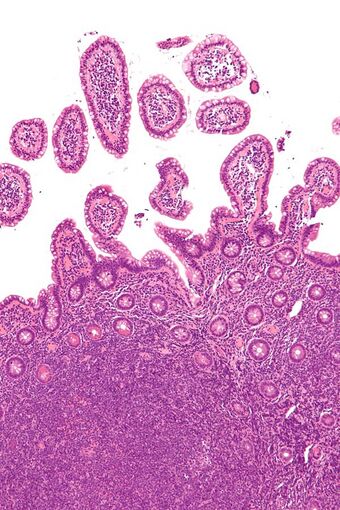

Micrograph of mantle cell lymphoma, a type of non-Hodgkin lymphoma. Terminal ileum. H&E stain. | |